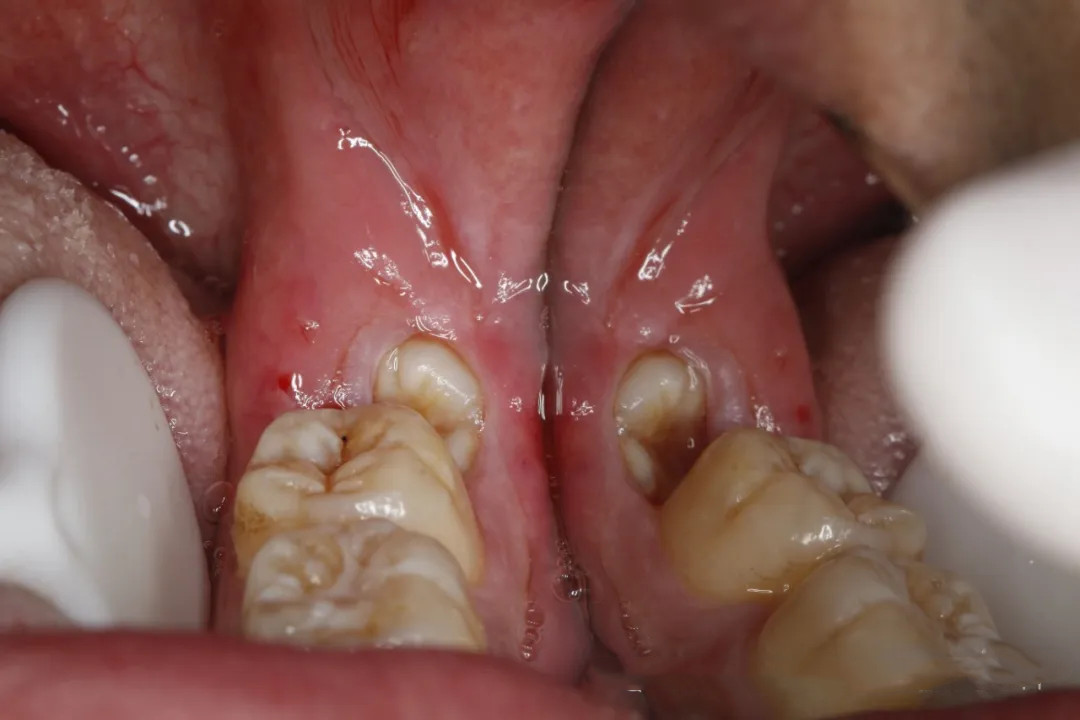

阻生齒部分萌出時(shí),其牙冠周圍的牙齦瓣與牙冠之間會(huì)形成一個(gè)特殊的盲袋。這個(gè)盲袋就像一個(gè)藏污納垢的角落,食物殘?jiān)鼧O易進(jìn)入,卻又很難被常規(guī)的刷牙、漱口等口腔清潔方式清除。細(xì)菌在盲袋內(nèi)大量滋生繁殖,便會(huì)引發(fā)炎癥,也就是智齒冠周炎。患者常常會(huì)出現(xiàn)牙齦紅腫、疼痛難忍的癥狀,嚴(yán)重時(shí)甚至連張口都會(huì)受限,吞咽也伴隨著疼痛,還可能伴有發(fā)熱、頜下淋巴結(jié)腫大等全身不適。如果冠周炎反復(fù)發(fā)作,不僅會(huì)嚴(yán)重干擾患者的日常生活與工作,比如影響進(jìn)食和說話,還可能導(dǎo)致感染擴(kuò)散,引發(fā)更為嚴(yán)重的口腔頜面部感染,如咬肌間隙感染等,使咬肌區(qū)腫脹疼痛,無法正常咬合。

阻生齒位置不正,常常會(huì)與鄰牙緊密接觸,而且此處清潔難度極大。食物殘?jiān)菀浊度谧枭X與鄰牙之間的縫隙里,細(xì)菌利用這些殘?jiān)a(chǎn)酸,逐漸腐蝕鄰牙的牙體組織,從而導(dǎo)致鄰牙發(fā)生齲壞。例如,下頜阻生智齒就可能致使第二磨牙遠(yuǎn)中鄰面齲壞。此外,部分阻生齒在生長過程中,其牙根會(huì)對(duì)鄰牙的牙根產(chǎn)生壓迫,使鄰牙牙根發(fā)生吸收。牙根吸收會(huì)使鄰牙的牙髓腔暴露,引發(fā)牙髓炎癥,同時(shí)削弱鄰牙的支持力,影響其穩(wěn)定性,嚴(yán)重時(shí)可導(dǎo)致鄰牙松動(dòng)甚至脫落。